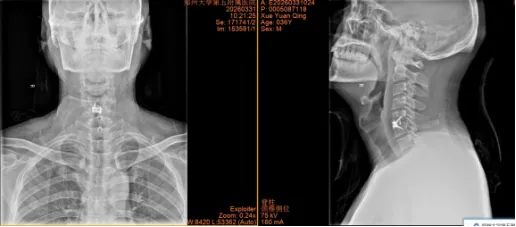

2.山西省晋城市沁水县龙港镇 44岁李女士

术前:依托高分辨率CT、MRI及神经电生理监测,进行三维可视化手术规划

术中:在超声骨刀辅助下开展颈前路、颈后路或后路+前路等术式,并在神经电生理监护下确保减压彻底、置钉安全。